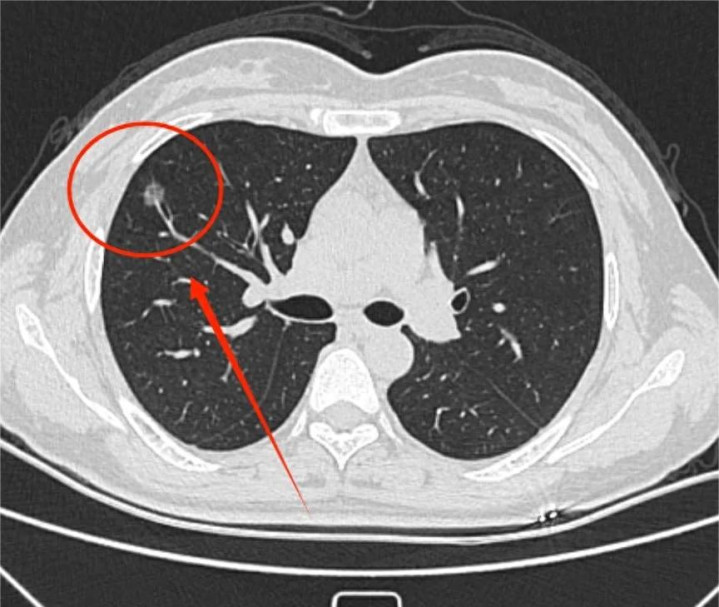

张先生,52岁,体检发现右肺下叶一枚8毫米夹杂磨玻璃结节。十分神焦,自述普通社交多,常感胸闷、咳极少白痰、躯壳困重,喉咙不深远,饭后尤其赫然。舌苔白腻,舌质暗红,边有齿痕,金年会(JinNianHui)体育这是典型的痰湿内盛、气滞血瘀之象。

他坚捏养息了三个多月,最赫然的感受是:胸闷消失了,咳痰赫然减少,扫数这个词东说念主大肆了不少。复查肺CT夸耀:右肺下叶夹杂磨玻璃结节松开至4毫米,实性要素经受,密度变淡,趋于消释。他惊喜地跟我说:“真没意料,中药合营这三种生果,后果能这样赫然!”